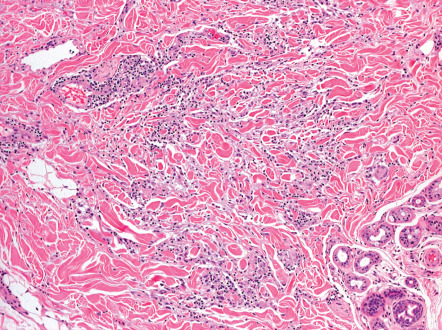

Pathology

GA is a granulomatous dermatitis characterized by focal degeneration of collagen and elastic fibers, mucin deposition, and a perivascular and interstitial lymphohistiocytic infiltrate in the upper and mid dermis. The key to the histopathologic diagnosis of GA is the presence of mucin plus the identification of histiocytes in one of two patterns. The most common (accounting for ~50–70% of cases) is the interstitial or infiltrative pattern ( Fig. 93.11 ), in which scattered histiocytes are distributed between collagen fibers. Degeneration of collagen fibers is minimal, but granular, basophilic mucin deposition between collagen bundles can be highlighted with Alcian blue and colloidal iron stains . The second pattern (25–50% of cases) is more obvious and is easier to diagnose. It consists of one to several palisading granulomas with central connective tissue degeneration surrounded by histiocytes and lymphocytes ( Fig. 93.12 ). Mucin is abundant in the center of the palisaded granuloma, and fibrin, neutrophils and nuclear dust may also be present.